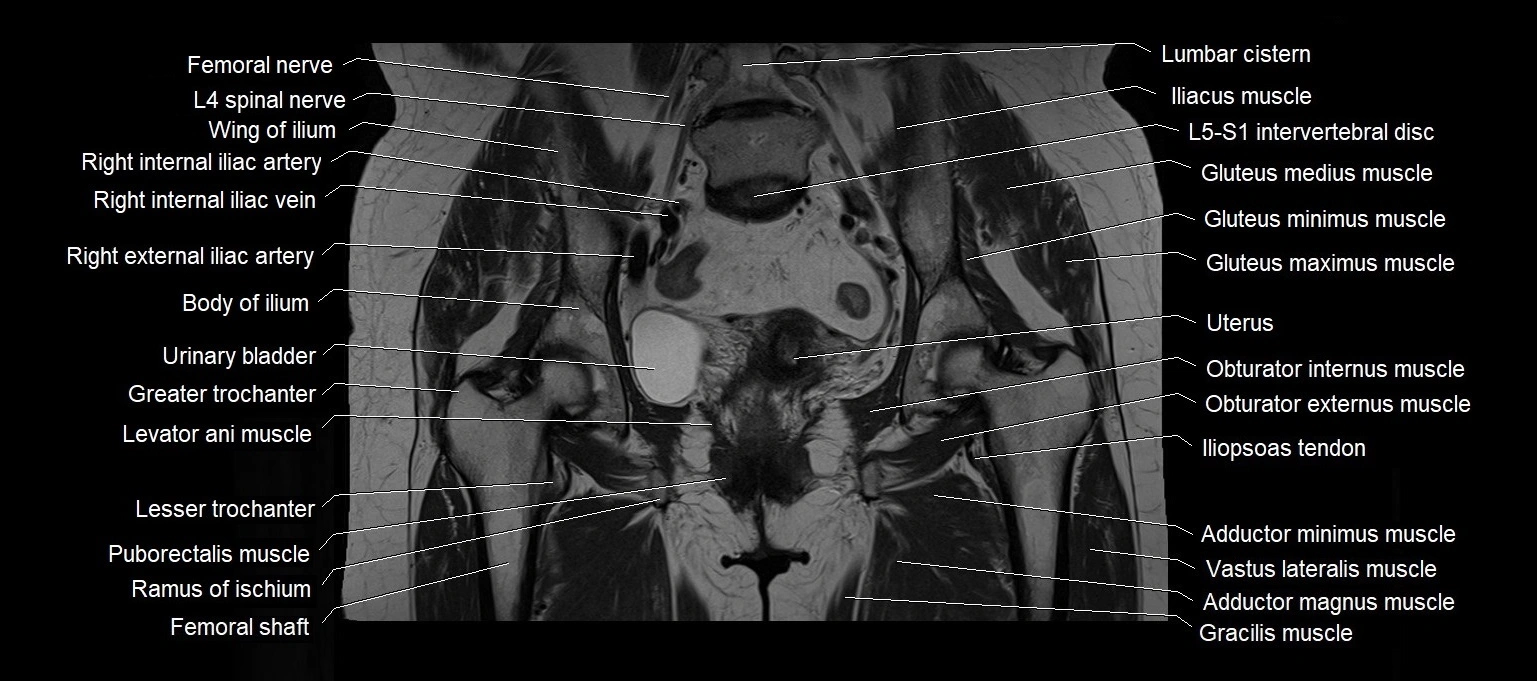

MRI images